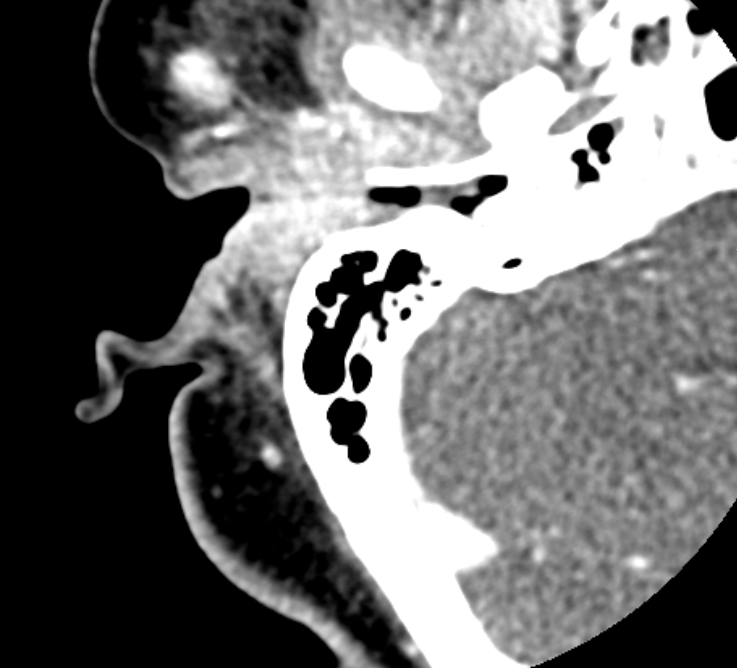

A 61 yo female with a history of DM presents with 3 days of severe R ear pain. She denies fever, but reports fullness, swelling and decreased hearing. Exam reveals significant swelling and tenderess of the R pinna and EAC without drainage. A CT is obtained. What's the diagnosis? (scroll down for answer)

Answer: Malignant Otitis Externa

- CT temporal bones can be used to evaluate extent of infection